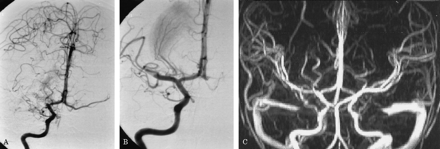

图2。(一)右颈内动脉血管造影披露血栓栓塞大脑中动脉(MCA)阻塞。(B)血管造影在动脉内的溶解(约20分钟后血管造影获得2 a所示)显示了MCA干线的血管再通和纹状体外动脉增外侧。(C) Postinterventional MR血管造影显示血管再通整个MCA的领土。